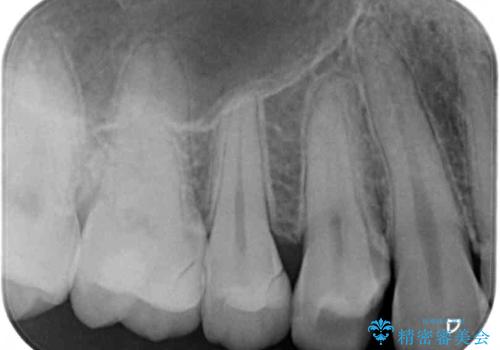

- 以前治療した詰め物が外れてしまい、冷たいものがしみることを主訴として来院された患者様です。

むし歯がないことを確認し、セラミックインレーにて修復するととしました。

適合の良いセラミックインレーの装着により、冷たいものがしみる症状はなくなりました。